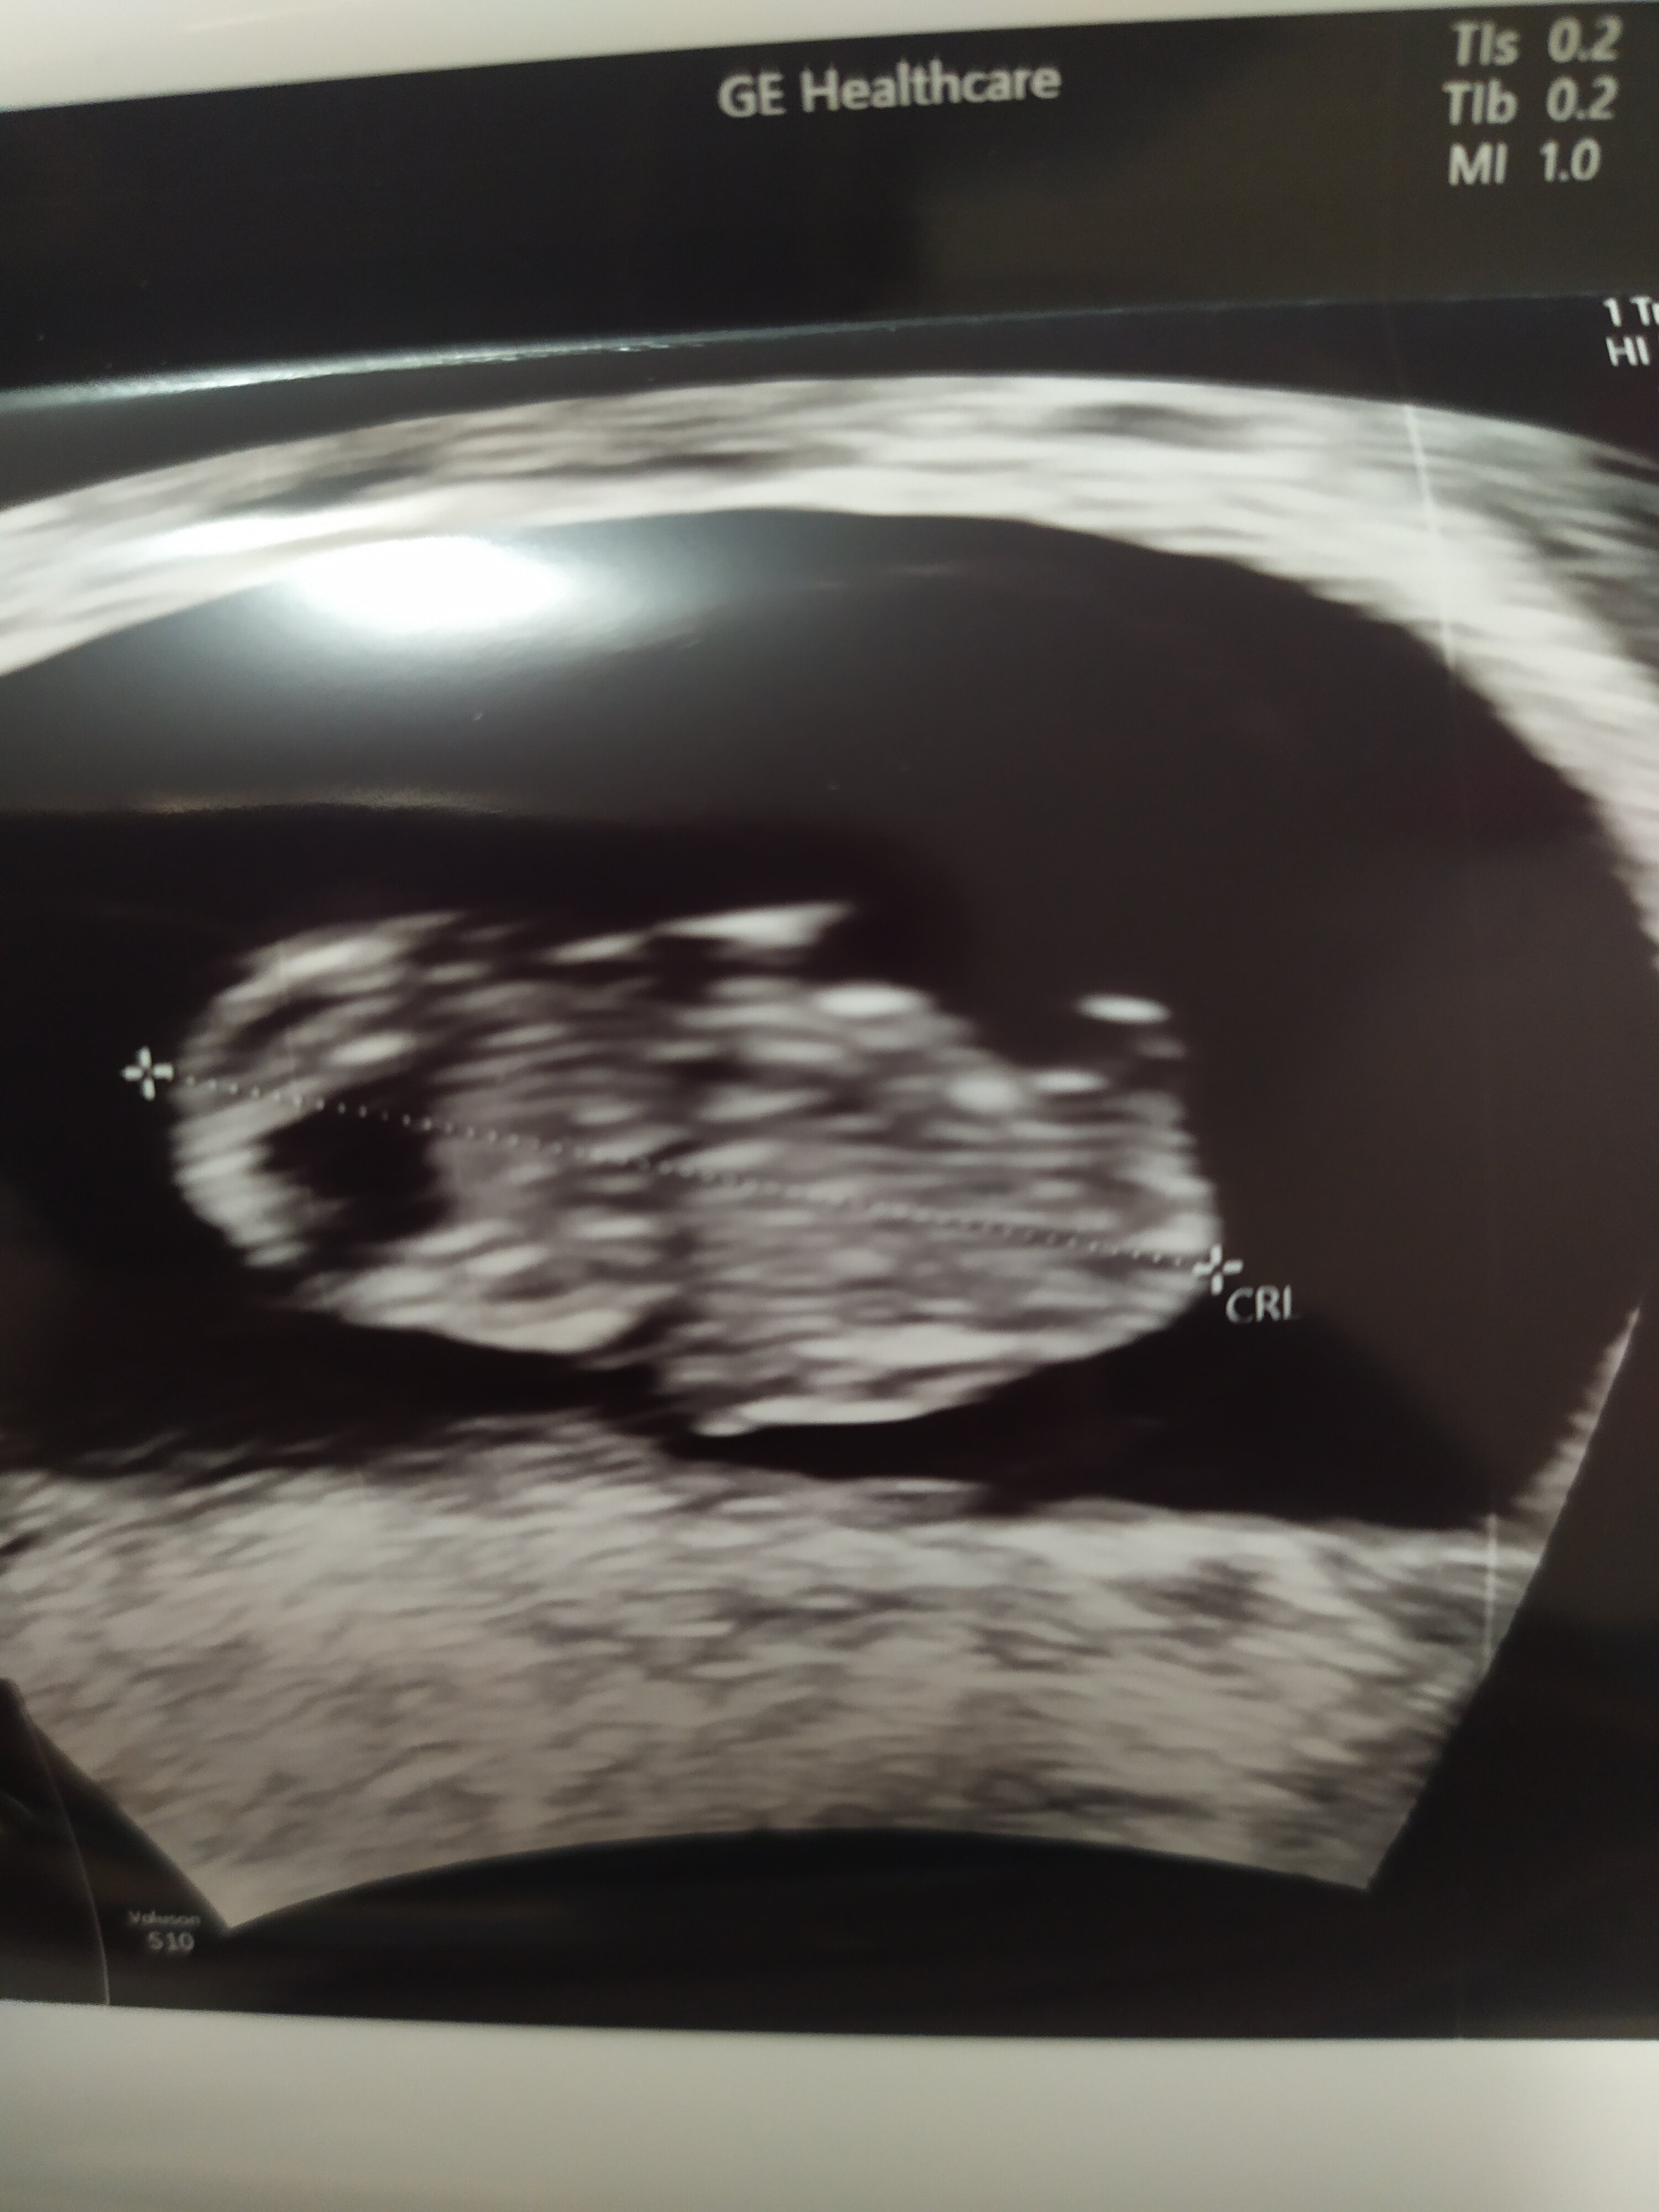

To mój dzisiejszy robak 😁 om 8+0, USG 8+4, więc jakby jednak marcowe 🤪 według aplikacji 8+3, więc 01.04. 🙃